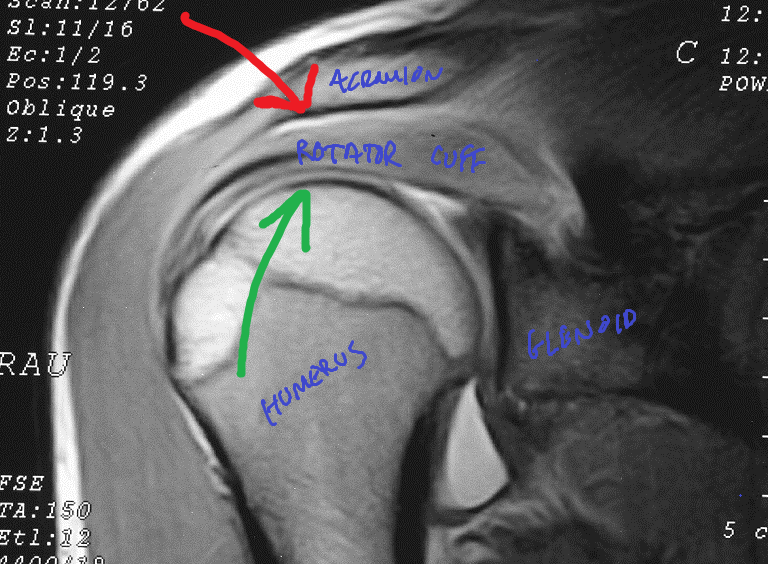

Shoulder Arthritis / Rotator Cuff Tears causes of shoulder pain How X Ray Shoulder Impingement Subacromial impingement is the most common cause of shoulder pain which occurs as a result of compression of the rotator cuff muscles by superior structures. Subacromial impingement is the most common form of shoulder impingement and occurs secondary to attrition between the. Shoulder impingement describes a group of conditions characterized by the entrapment of musculoskeletal soft tissue. Impingement syndrome is. X Ray Shoulder Impingement.